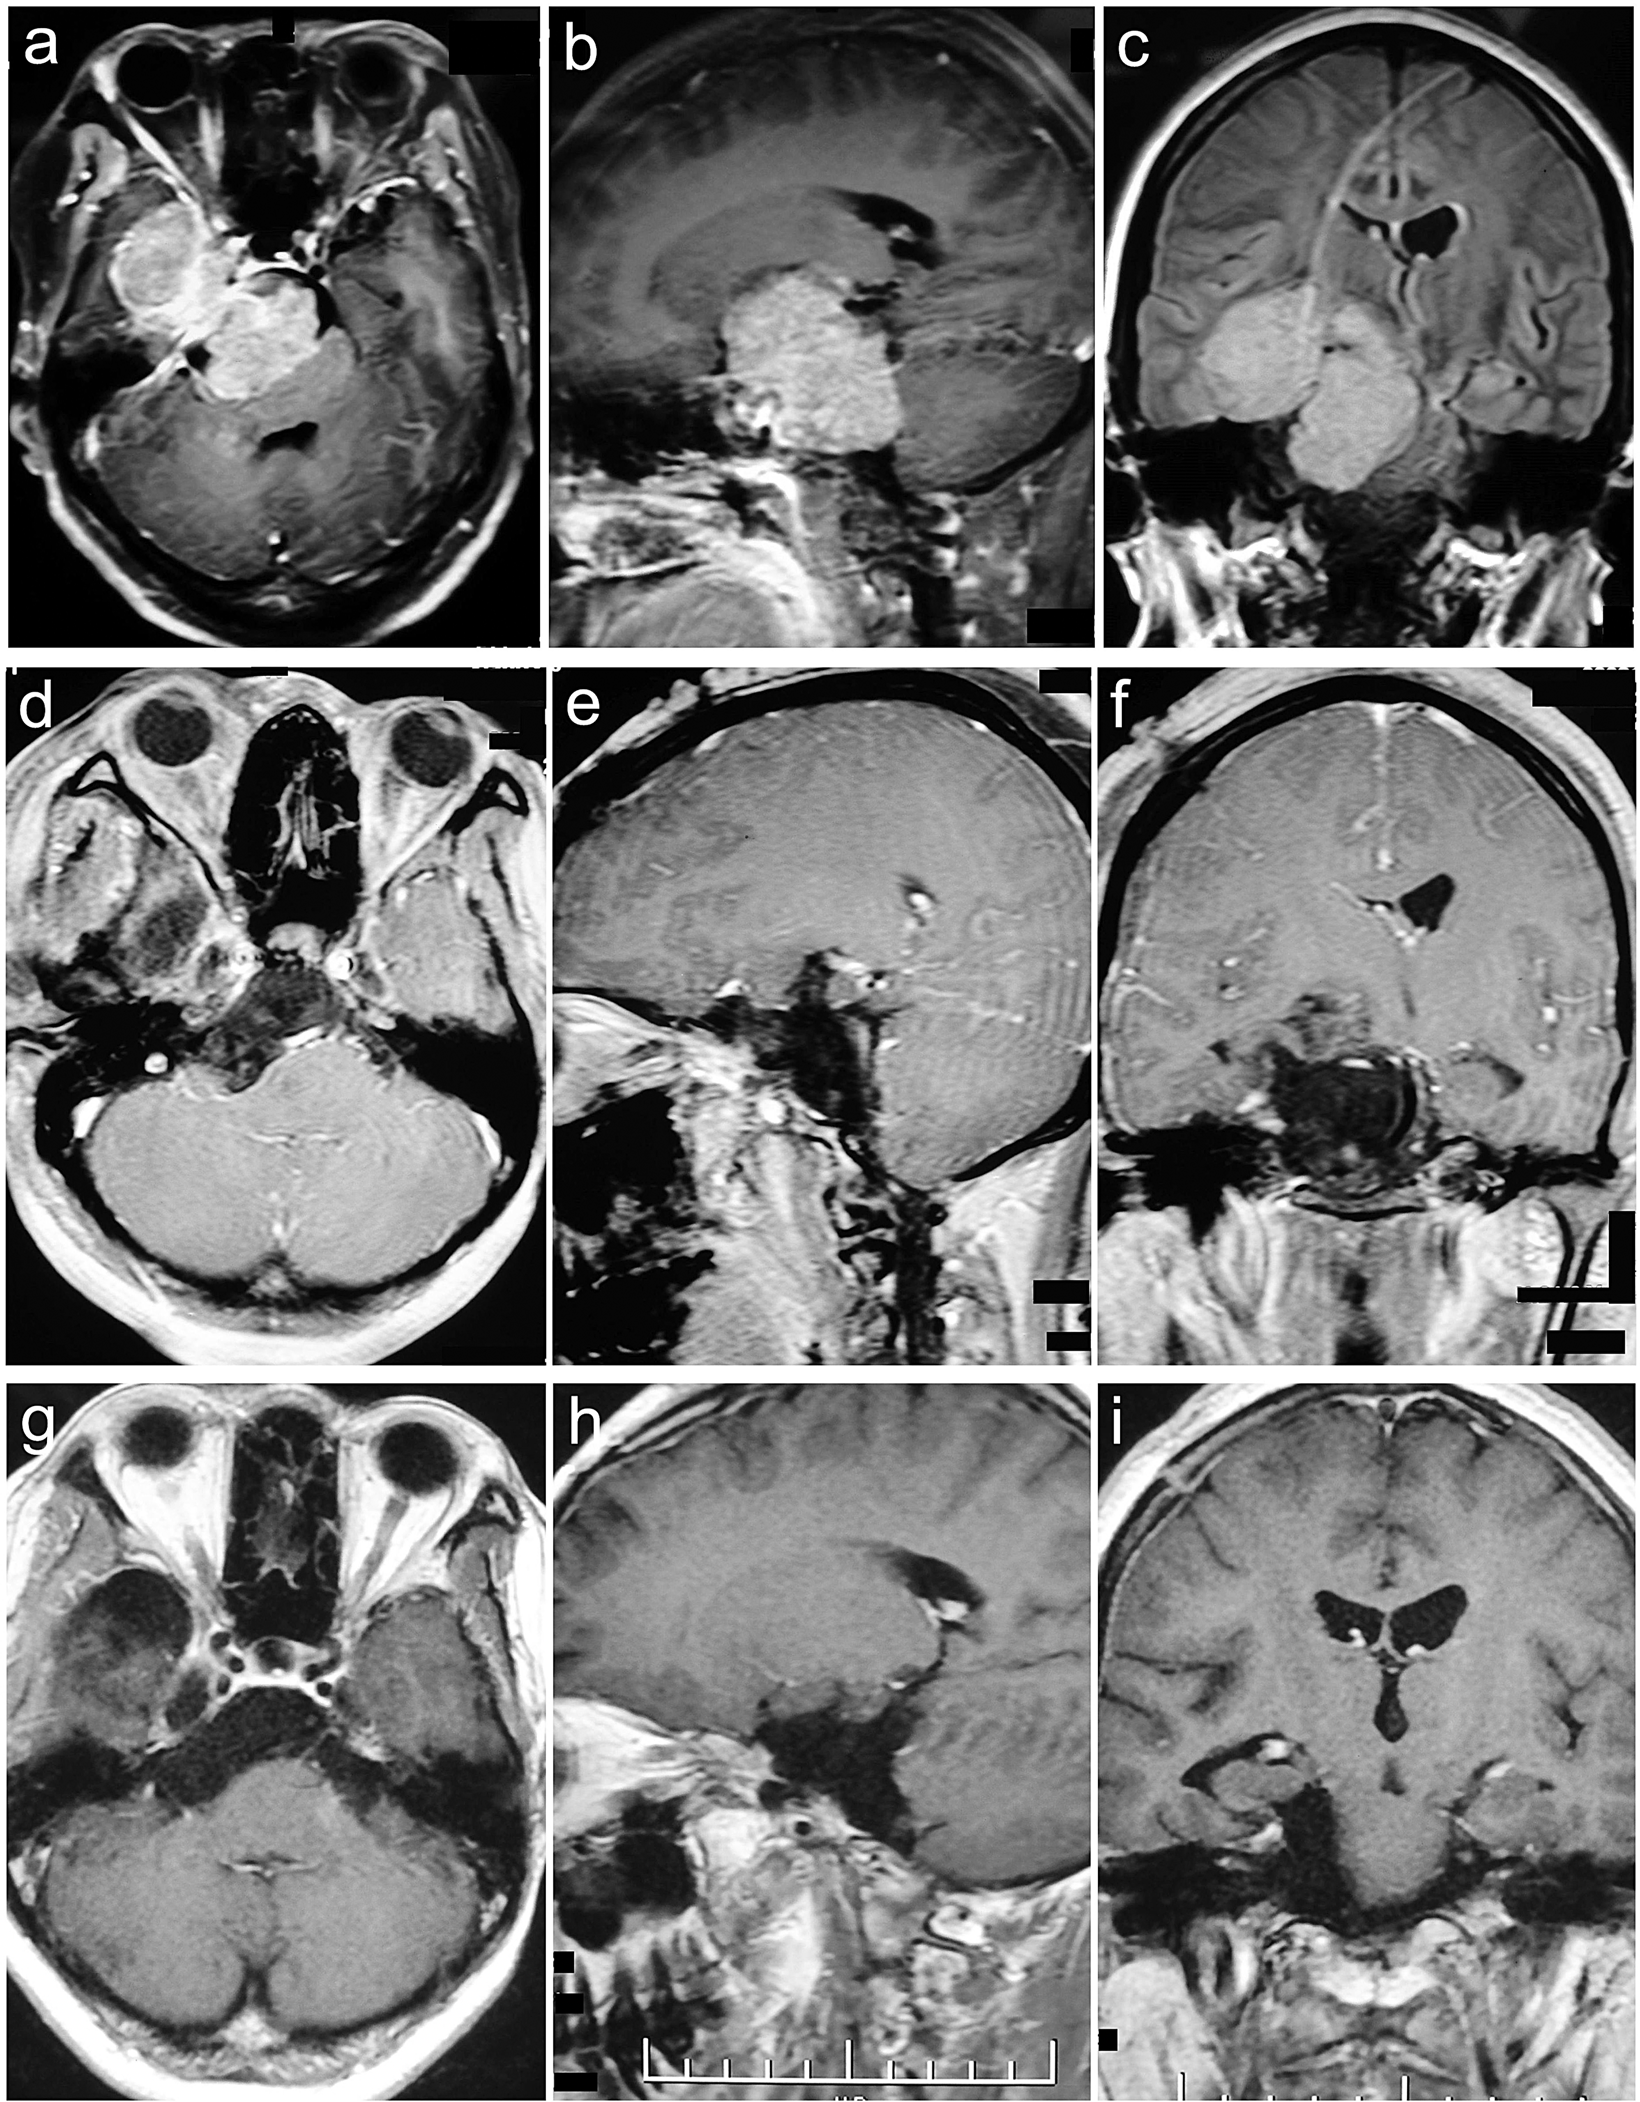

Figure 8

Sphenopetroclival subtype II case. A 41-year-old female presented with epilepsy for 7 months. The preoperative KPS score was 70. She was achieved GTR with the EPTA. The postoperative KPS score was 60. With a follow-up of 30 months, she participated in normal activities and had a KPS score of 90 without recurrence. (a–c) Preoperative MRI T1 contrast axial, sagittal, and coronal images. (d–f) Postoperative MRI T1 contrast axial, sagittal, and coronal images. (g–i) Follow-up MRI T1 contrast axial, sagittal, and coronal images.